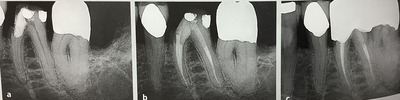

根管治療が上手くいきそうか?技術的に難しい点は?を調べるには、

レントゲンをよ〜く見るのが欠かせません。

バイトウイング、咬翼法、上下の奥歯を咬んだ状態で真横から撮る方法です。

この方法が残っている歯を状態を見るには、一番です。

神経の部屋、歯髄腔の状態、

歯を被せられる?に大切な歯頚部、歯の頭と根っこの継ぎ目、ウエスト部分の状態、

虫歯がどこまで進んでいるのか?

特に根っこにまで進んでいるのか?骨の近くや根っこの分かれ目に近いのか?を見る時にです。

真ん中のが、バイトウイング法です。

根元部分や神経の頭の部屋などが、よく分かります。

歯の間の虫歯を調べるには、1番です。

左のレントゲンでは、黒い虫歯が大きくて残せないかも?

でも真ん中から、まだ骨や分岐部、根っこの分かれ目まで進んでいないと分かります。

なので根管治療をして残す事ができました。